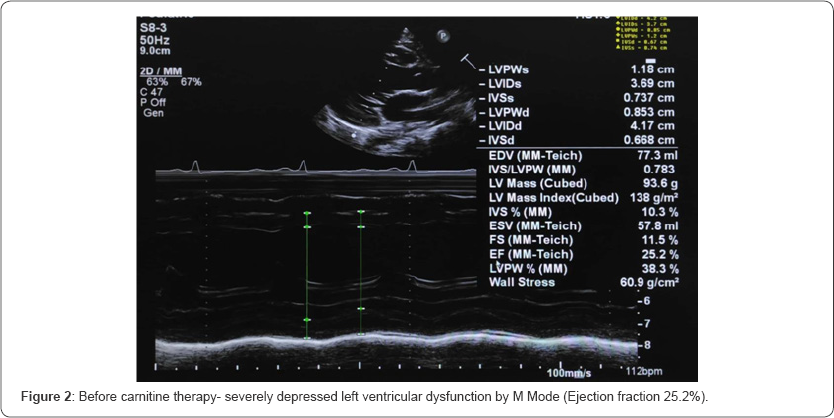

Her initial echocardiogram revealed severe depressed LV dysfunction- Ejection Fraction (EF) by modified Simpsons {24.3%}, M mode EF {24.2%} (Figure 1 &2). In relation to her hypertension related to end-stage renal failure, she is maintained on angiotensin-converting enzyme inhibitors. Further, she was investigated for carnitine levels which confirmed secondary carnitine deficiency (Table 1). After the 6 months trial of 20mg/kg of intravenous carnitine for 5 times a week (end of dialysis) leads to remarkable improvement in IH episodes and cardiac function. Her repeated echocardiogram revealed improved LV function- modified Simpsons {54.1%}, M mode EF {50.4%} (Figure 3 & 4).